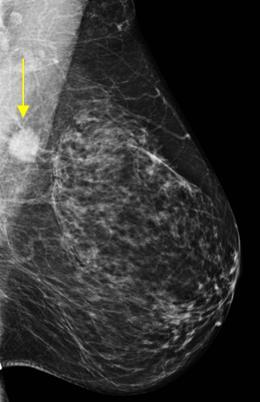

Ung thư vú

Ung thư vú - Ảnh 5

» Thông tin: Nữ giới – 51 tuổi.

» Lâm sàng: Khối tuyến vú.